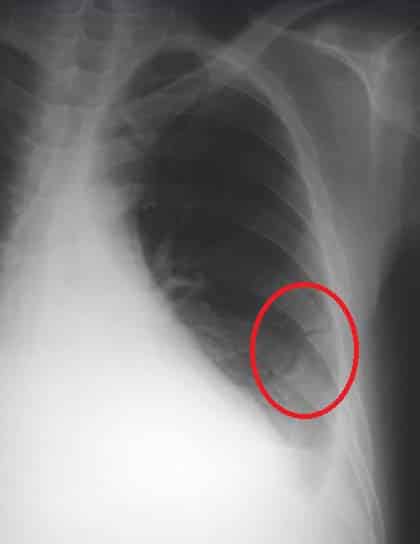

The ribs are a set of twelve paired bones which form the protective ‘cage’ of the thorax. They articulate with the vertebral column posteriorly, and terminate anteriorly as cartilage (known as costal cartilage). As part of the bony thorax, the ribs protect the internal thoracic organs. They also have a role in ventilation; moving during chest expansion to enable lung inflation. In this article, we shall look at the anatomy of the ribs – their bony landmarks, articulations and clinical correlations. By TeachMeSeries Ltd (2025) Fig 1Overview of the ribs and costal cartilage. Pro Feature - 3D Model You've Discovered a Pro Feature Access our 3D Model Library Explore, cut, dissect, annotate and manipulate our 3D models to visualise anatomy in a dynamic, interactive way. Learn More Rib Structure There are two classifications of ribs – atypical and typical. The typical ribs have a generalised structure, while the atypical ribs have variations on this structure. Typical Ribs The typical rib consists of a head, neck and body: The head is wedge shaped, and has two articular facets separated by a wedge of bone. One facet articulates with the numerically corresponding vertebra, and the other articulates with the vertebra above. The neck contains no bony prominences, but simply connects the head with the body. Where the neck meets the body there is a roughed tubercle, with a facet for articulation with the transverse process of the corresponding vertebra. The body, or shaft of the rib is flat and curved. The internal surface of the shaft has a groove for the neurovascular supply of the thorax, protecting the vessels and nerves from damage. By TeachMeSeries Ltd (2025) Fig 2The bony landmarks of a typical rib. Atypical Ribs Ribs 1, 2, 10 11 and 12 can be described as ‘atypical’ – they have features that are not common to all the ribs. Rib 1 is shorter and wider than the other ribs. It only has one facet on its head for articulation with its corresponding vertebra (there isn’t a thoracic vertebra above it). The superior surface is marked by two grooves, which make way for the subclavian vessels. Rib 2 is thinner and longer than rib 1, and has two articular facets on the head as normal. It has a roughened area on its upper surface, from which the serratus anterior muscle originates. Rib 10 only has one facet – for articulation with its numerically corresponding vertebra. Ribs 11 and 12 have no neck, and only contain one facet, which is for articulation with their corresponding vertebra. Pro Feature - Dissection Images The left sympathetic chain (sympathetic trunk) located on the internal surface of the posterior thoracic wall. The intercostal neurovascular bundle is visible on the internal surface of each rib. The left sympathetic chain (sympathetic trunk) located on the internal surface of the posterior thoracic wall. The intercostal neurovascular bundle is visible on the internal surface of each rib. You've Discovered a Pro Feature Access our Dissection Image Library Enhance your understanding with high-resolution dissection images showcasing real-life anatomy. Learn More Articulations The majority of the ribs have an anterior and posterior articulation. Posterior All the twelve ribs articulate posteriorly with the vertebra of the spine. Each rib forms two joints: Costotransverse joint – between the tubercle of the rib, and the transverse costal facet of the corresponding vertebra. Costovertebral joint – between the head of the rib, superior costal facet of the corresponding vertebra, and the inferior costal facet of the vertebra above. By TeachMeSeries Ltd (2025) Fig 3Posterior articulations between a typical rib and its numerically corresponding vertebra. Anterior The anterior attachment of the ribs vary: Ribs 1-7 attach independently to the sternum. Ribs 8 – 10 attach to the costal cartilages superior to them. Ribs 11 and 12 do not have an anterior attachment and end in the abdominal musculature. Because of this, they are sometimes called ‘floating ribs’. Clinical Relevance Rib Fractures Rib fractures most commonly occur in the middle ribs, as a consequence of crushing injuries or direct trauma. A common complication of a rib fracture is further soft tissue injury from the broken fragments. Structures most at risk of damage are the lungs, spleen or diaphragm. If two or more fractures occur in two or more adjacent ribs, the affected area is no longer under control of the thoracic muscles. It displays a paradoxical movement during lung inflation and deflation. This condition is known as flail chest. It impairs full expansion of the ribcage, thus affecting the oxygen content of the blood. Flail chest is treated by fixing the affected ribs, preventing their paradoxical movement. By James Heilman [CC-BY-SA-3.0], via Wikimedia Commons Fig 4Chest radiograph of multiple fractured ribs, producing ‘flail chest’ Do you think you’re ready? Take the quiz below Pro Feature - Quiz The Ribs Question 1 of 3 Submitting... Skip Next Rate question: You scored 0% Skipped: 0/3 1800 More Questions Available Upgrade to TeachMeAnatomy Pro Challenge yourself with over 1800 multiple-choice questions to reinforce learning Learn More Rate This Article